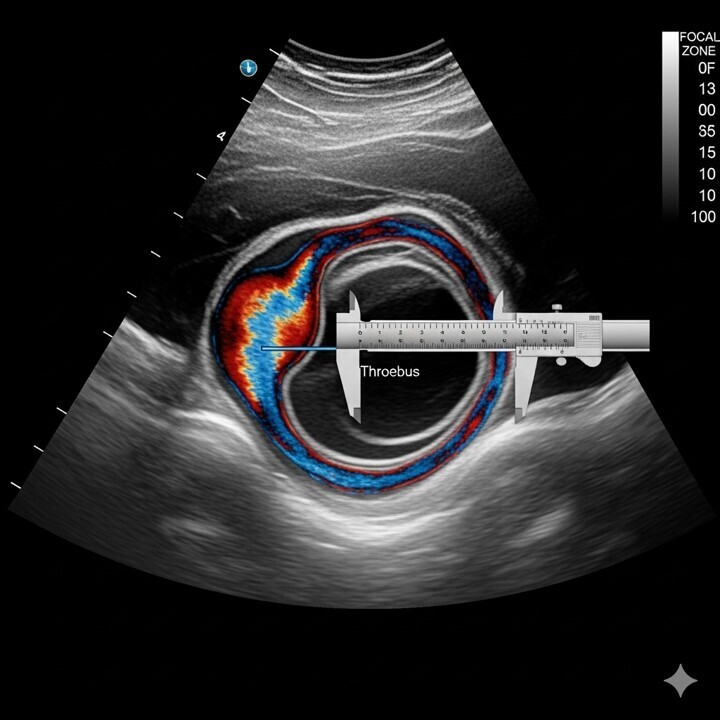

1/ Le dépistage des anévrismes de l'aorte abdominale. C'est l'examen référence , non irradiant, non invasif et d'une grande fiabilité. peu couteux.

La mesure de diamètre antéro-postérieur (DAP) est le diamètre référence, paroi externe/paroi externe.

Cette mesure doit se faire en mode B et en mode TM, cette dernière est la technique la plus fiable.

Si on détecte la présence d'un anévrysme, contrôle écho- Doppler des vaisseaux du cou, des artères des MI avec recherche d'autres anévrismes